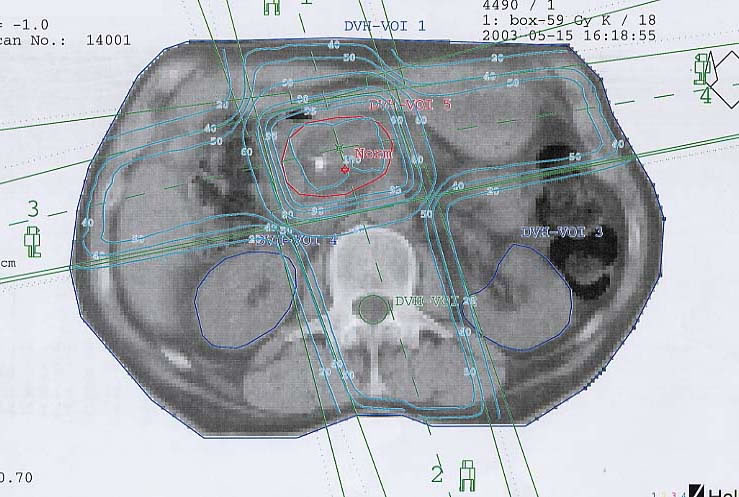

Tumore der Bauchspeicheldrüse (Pankreas): Bestrahlungsplan